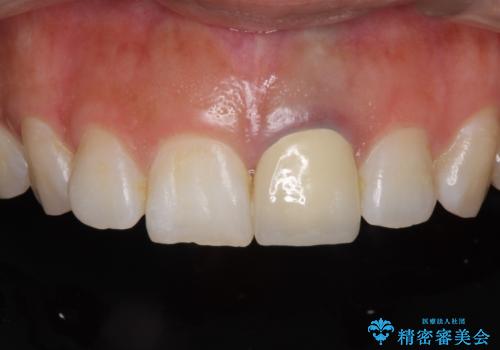

今回は歯自体が黒くなって歯茎から透けて見えている黒ずみのため、セラミック治療で改善させることは困難だというお話をしました。その上でできる範囲できれいに治療することになりました。

今回のように歯自体が金属イオンで黒く変色すると、被せものをメタルフリーにしても黒ずみをすべて隠すのは困難になります。一方、被せものの金属が見えていることが原因の黒ずみの場合は、セラミック治療できれいになりますので、気になる方は一度ご来院ください。